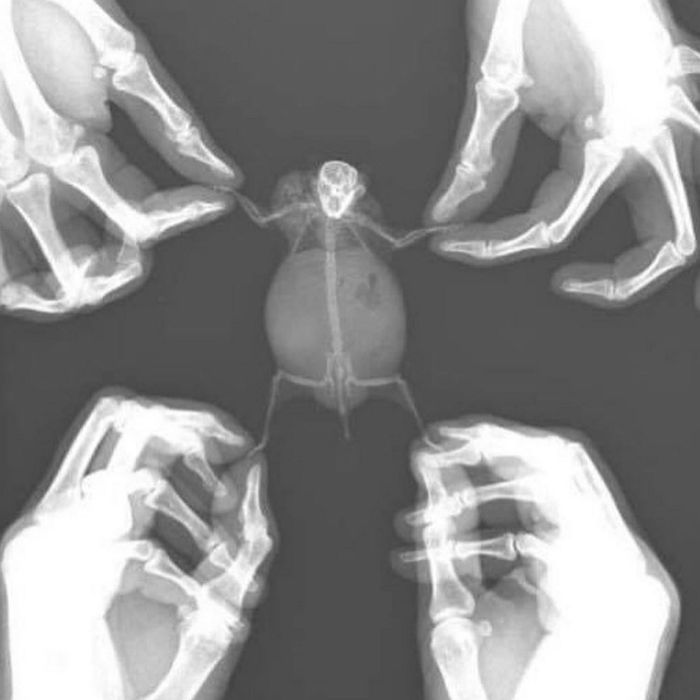

아파서 병원 온 햄찌를 보고

모두들 심쿵한 사연이 있는데요.

아픈건 슬프지만 녀석을 엑스레이 찍는

순간 아기자기한 모습에

그만 심장이 쿵 내려앉는 듯 하네요.

어쩜 몸속 뼈까지 저리

귀엽게 아기자기할까요.

햄찌를 엑스레이 찍었더니

이런 모습이 나왔다고 하는데요.

정말 귀여우면서도 신기할 따름입니다.

햄찌가 얼른 빨리 치료해서 마구마구

뛰어다닐 수 있었으면 좋겠습니다.